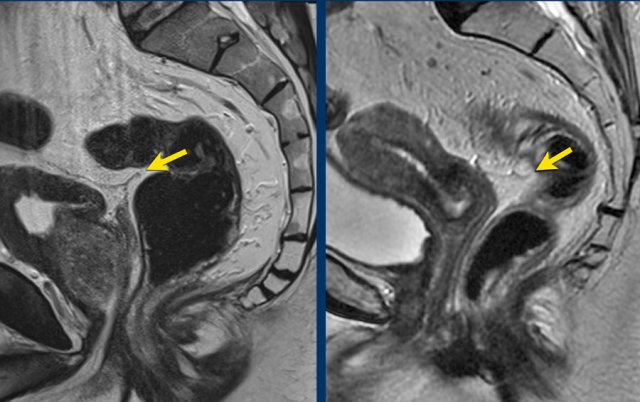

Images

The image on the left shows a tumor with a close relation to the peritoneum and the bladder (white arrow).

However there is no tumor extension beyond the muscularis propria anteriorly and the peritoneum is therefore not invaded.

The image on the right shows definite tumor invasion of the peritoneum (yellow arrow), i.e. a T4a tumor.